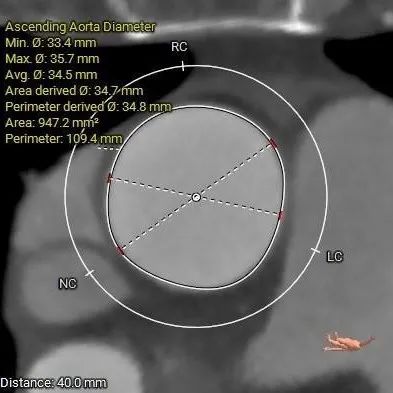

术前CT评估

主动脉根部总览

中度钙化,钙化主要分布于左、无瓣叶及R-N交界处

主动脉根部测量

三叶式主动脉瓣,瓣叶增厚,水平夹角42°;LVOT微微敞口

主动脉弓测量

主动脉弓部宽度、角度可

外周入路

腹主-双侧髂总动脉有少量钙化,股-髂动脉走行、内径可

• 三叶式主动脉瓣,R-N瓣叶交界部分粘连,瓣叶增厚伴中度钙化,钙化主要分布于左、无瓣叶及R-N交界处;LVOT微微敞口;

• 冠脉开口高度尚可,切线角度测量,无冗长瓣叶;冠脉远端有钙化分布

• 瓦氏窦、STJ内径尚可,升主动脉无扩张

• 收缩期左心室内径偏大,EF值45%

• 拟主动脉瓣水平夹角约42°,非横位心,主动脉弓宽度角度可

• 腹主-双侧髂总动脉有少量钙化,股-髂动脉走行、内径可。